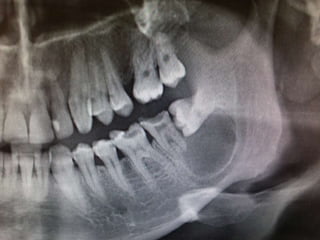

ÇENE KİSTLERİ | PPT